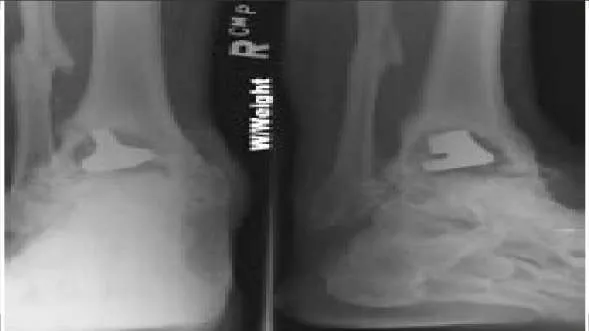

A 61-year-old woman presents for treatment of a painful ankle. She reports that 4 years ago, she sustained a fracture of her ankle that was treated with cast immobilization. She has experienced progressively worsening pain over the past 2 years. On examination, she has good range of motion of the ankle with crepitus and pain. Radiographs are presented (Slide 1 and Slide 2). All of the following are acceptable forms of surgical correction except:

Options:

- Supramalleolar osteotomy of the tibia

- Ankle arthroscopy

- Ankle arthrodesis

- Total ankle replacement

- Distraction lengthening osteotomy of the fibula

Correct Answer: Ankle arthroscopy

Explanation:

Each of the alternatives presented is reasonable except for ankle arthroscopy because it has a limited role in the management of posttraumatic arthritis of the ankle. In this patient, there is a possibility to salvage the ankle before arthrodesis or joint replacement with an osteotomy of the tibia and or the fibula. Both have a definite role in management of ankle deformity and arthritis. A closing wedge osteotomy of the tibia was performed in this patient, and she remains asymptomatic 4 years later (Slide 3 and Slide 4).